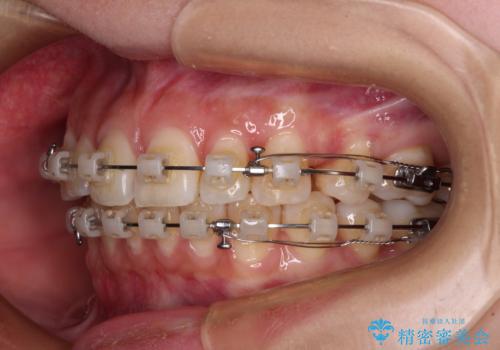

- 矯正装置

- クリアブラケット

- 治療計画

- 口を閉じたときに唇の間から飛び出してくる前歯を気にして来院された患者様です。

骨格的に上顎骨が前方位にあるため、左右の第一小臼歯を抜歯し、ワイヤー装置にて咬み合わせを整えていくこととしました。